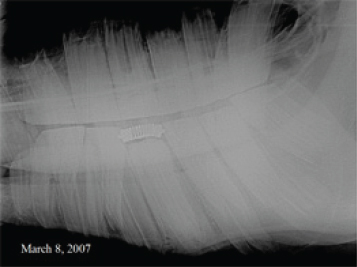

Weekly exams over a 3-month period showed no signs of any eruption of this tooth. Radiographs show that there are disturbing root changes consisting of distortion and blunting that may be hindering the eruption of this 308. A decision was made to surgically remove that distal potion of the root, followed by a root canal. An apicoectomy was performed on the 308 by removing a section of bone from the lateral mandible to expose the root. The skin and periosteum were elevated away from the bone, which created a proximal flap that would be sutured back into place after the apicoectomy and root canal were completed. The distal portion of the root was cut off just above the distorted area with a diamond cut off wheel. The cut was angled to allow better exposure of the pulp chambers for the root canal. Post surgical x-rays show the portion of root removed and the composite placed in the pulp cavities.

This surgical procedure was performed with the horse standing, using sedation and local anesthesia. This horse was difficult to handle and was reluctant to be caught prior to the surgery. He noticeably had an immediate change in disposition, which indicates relief of pain. The distorted root was caused by pressure from the inability of normal eruption to occur, which creates inflammation and pain. In my experience, most trapped premolars eventually abscess and form a drain tract through the distal mandible below the root if they are not extracted. Figures 185, 186, 187